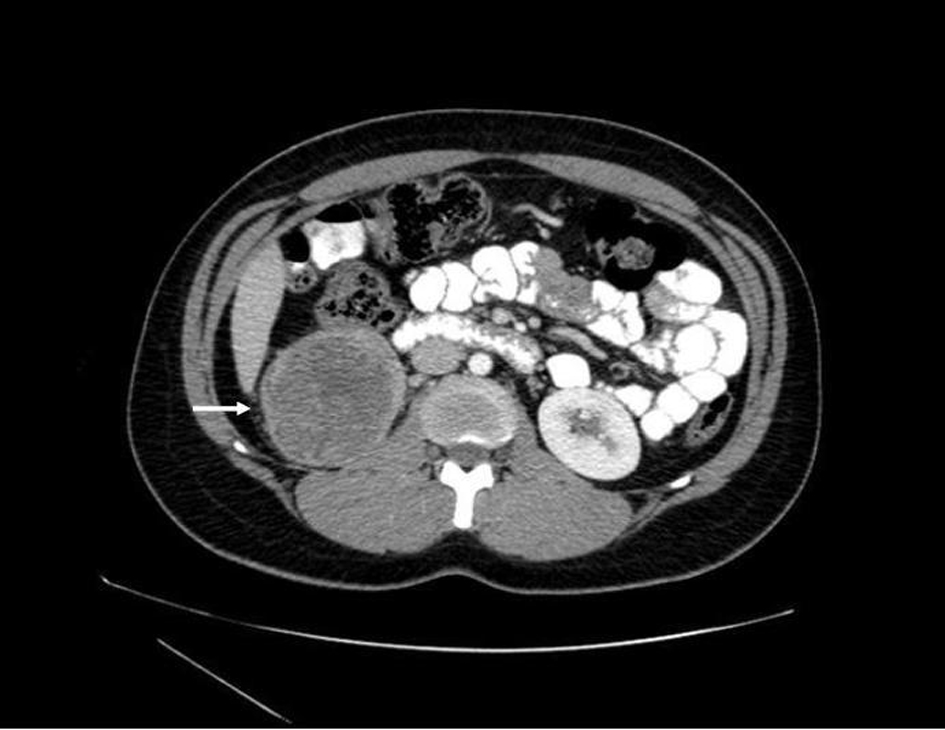

Prior to treatment, she underwent contrast enhanced staging CT of the abdomen and pelvis which revealed a 6.7 × 6.9 cm mass arising from the lower pole of the right kidney (Fig. 3, 4). Given the patient’s young age, history of sickle cell trait, radiologic findings of a large renal mass, multiple lung and breast nodules as well as the histological picture, the diagnosis of metastatic renal medullary carcinoma was considered. At this time, the original breast core biopsies were re-reviewed. Histological findings of prominent neutrophilic infiltrate closely associated with the tumor and sickled erythrocytes were identified. An additional immunohistochemical panel of PAX 8, vimentin, gross cystic disease fluid protein (GCDFP), Oct 3/4 and INI1 (BAF47) was performed. Positive expression of PAX 8 (nuclear) (Fig. 1b), vimentin (cytoplasmic and membranous), Oct3/4 (nuclear) (Fig. 1c) and loss of INI1 expression (Fig. 1d) in tumor cells confirmed the diagnosis of renal medullary carcinoma metastatic to breast [6-8].

![]() Click for large image | Figure 3. Axial CT (with oral and intravenous contrast enhancement) showing a 6.7 × 6.9 cm heterogeneous exophytic mass with areas of central low attenuation arising from the lower pole of the right kidney, with areas of central necrosis. |